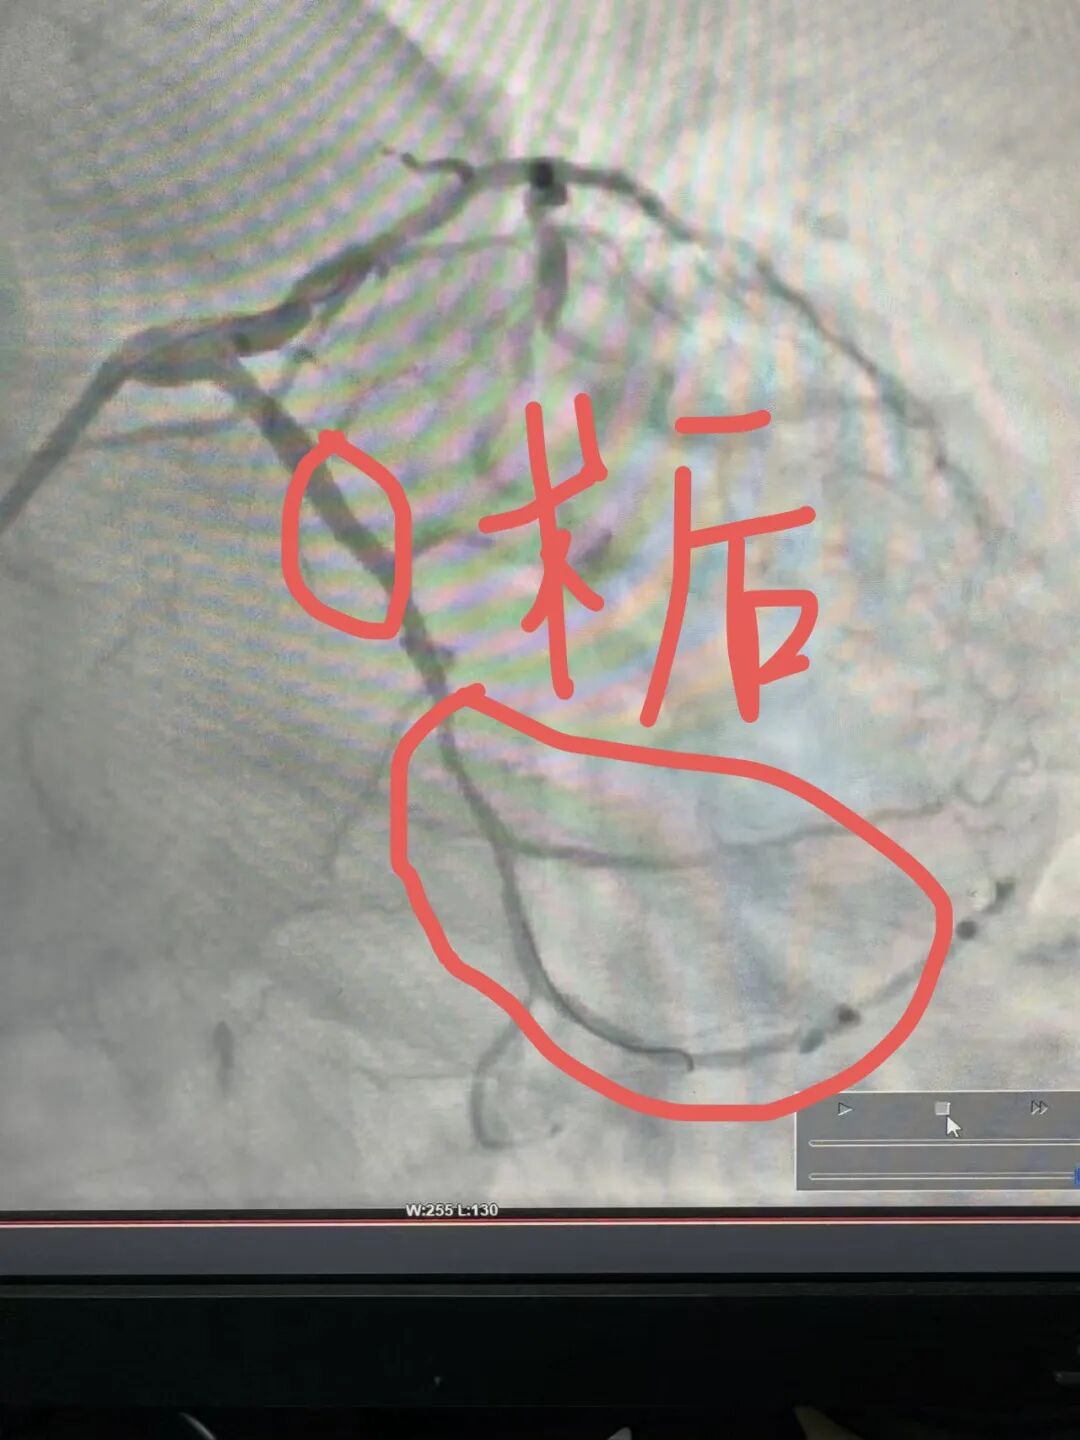

介入术中发现,在常规右侧桡动脉入路时,发现患者的桡动脉、肱动脉、锁骨下动脉血管严重扭曲,仿佛是一条蜿蜒曲折、布满荆棘的山路,导丝难以通过,手术一度受阻。关键时刻,介入团队冷静应对,主治医师罗科伟凭借娴熟技术与对血管结构的精确把握,耐心调整导丝方向,最终顺利将其送至主动脉根部,成功完成造影。

结果显示,患者回旋支严重狭窄,远段完全闭塞,心肌供血严重不足。团队随即决定在病变处施行药物球囊扩张联合药物洗脱支架植入术。经过精细操作,血管狭窄解除,血流恢复通畅。术后患者胸痛症状明显缓解,恢复良好。